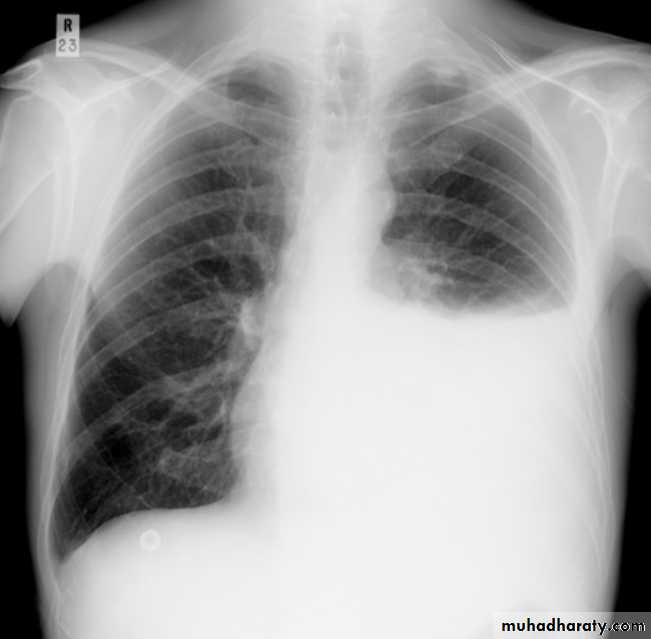

Plain radiographChest radiographs are the most commonly used examination to assess for presence of a pleural effusion, however it should be noted that on a routine erect chest x-ray as much as 250-600 ml of fluid is required before it becomes evident 6. A lateral decubitus film is most sensitive, able to identify even a small amount of fluid. At the other extreme, supine films can mask large quantities of fluid.

Both PA and AP erect films are insensitive to small amounts of fluid. Features include:

blunting of the costophrenic angle

blunting of the cardiophrenic angle

fluid within the horizontal or oblique fissures

eventually a meniscus will be seen, on frontal films seen laterally and gently sloping medially (note:

with large volume effusions, mediastinal shift occurs away from the effusion (note: if coexistent collapse dominates then mediastinal shift may occur towards the effusion)